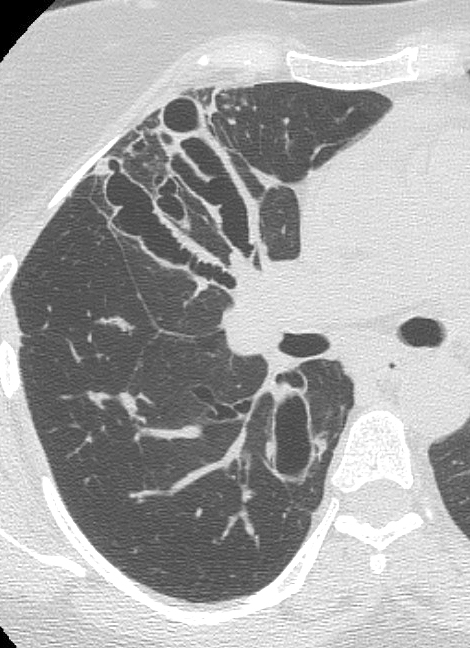

ABPA CT